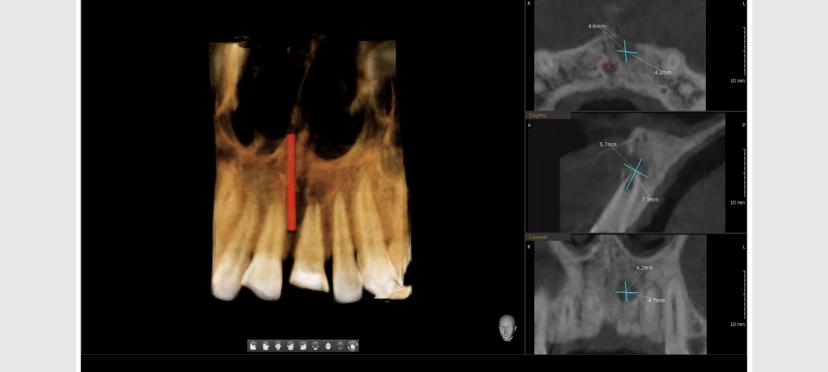

Fibro Osseous Lesions

Fracture of Teeth

Implant Planning